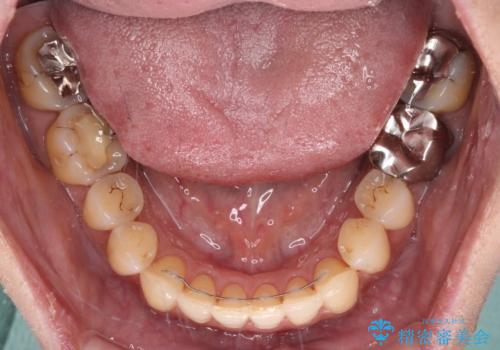

舌側転位している側切歯特有の、切縁の位置が不揃いであったり、根元が内側に引っ込んだ状態であったりという、インビザライン独特の仕上がりになることなく、きれいに整った歯列とすることができました。